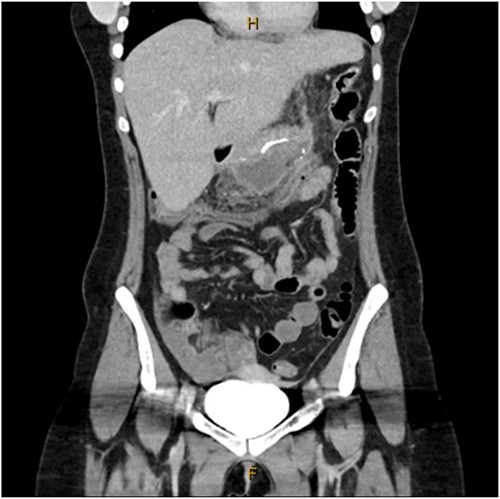

A 31-year-old female, 6 weeks post laparoscopic sleeve gastrectomy presented to the emergency department with epigastric pain and vomiting. Initial bloods showed raised inflammatory markers with a white cell count of 15.5 × 109/L and C-reactive protein of 342 mg/L. Initial CT on presentation showed the presence of a 14 × 7 × 5 cm3 gas and fluid filled collection adjacent to the staple line (Fig. 1). The patient was resuscitated with adequate fluids and kept nil by mouth. Prompt broad spectrum antibiotics were commenced. An 8Fr firm nasobiliary tube was placed directly into the collection via the defect near the GOJ under endoscopic guidance and placed on suction. During the same endoscopic procedure, a feeding nasojejunal tube was placed to ensure adequate nutrition. Given the extent of the collection, sequential advancement of the nasobiliary tube over the course of 23 days was required to ensure adequate drainage. The collection was monitored with repeat CT scans until resolution (Fig. 2). The GOJ defect was then endoscopically closed with an over the scope clip on Day 23 post presentation. The patient was discharged home post a repeat CT showing complete resolution of the collection and no oral contrast medium extending into the site of the previous collection.

Coronal CT images on Days 2, 9 and 14 post insertion of nasobiliary drainage tube to sleeve gastrectomy staple line collection showing interval reduction in collection size.